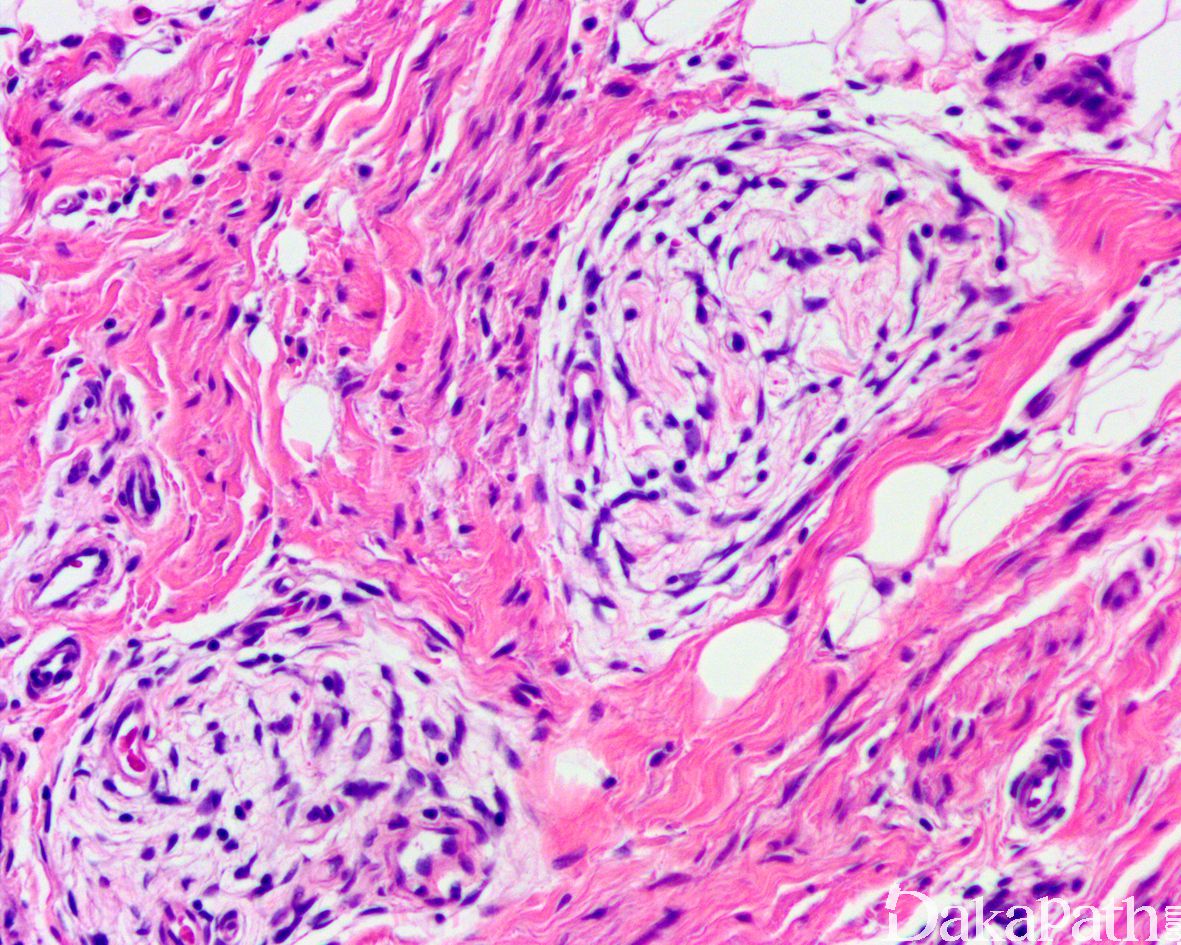

致密的纤维组织由比较成熟的纤维母细胞、肌纤维母细胞和胶原纤维组成,呈纵横交错的束状排列,常呈指状伸入脂肪组织内,组织学类似于纤维瘤病;部分区域可见梭形细胞之间成片的胶原化或瘢痕化以及多核巨细胞沉积,类似于乳腺的假血管瘤样增生或巨细胞纤维母细胞瘤样改变;

原始间叶组织呈结节状分布,由幼稚的短梭形、卵圆形或星状细胞排列成呈疏松的漩涡状、巢状或宽带状包被于富于血管的黏液性基质之间;

瘤细胞形态均教温和,核异型性轻微,罕见核分裂象;